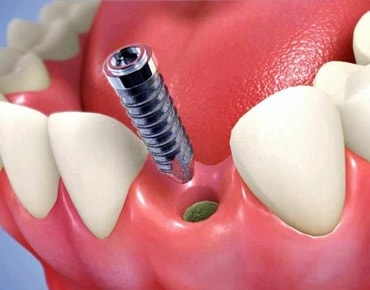

インプラントとは、顎の骨に人工歯根となる金属を埋め込み、その金属を土台にして、天然の歯と同じような人工の歯を取り付ける治療方法です。

埋め込む金属に生体との親和性が高いチタンが使われる事が多く、チタンは長年の臨床研究でインプラントの素材として最も安全であり、また顎の骨としっかり結合することが確認されています。